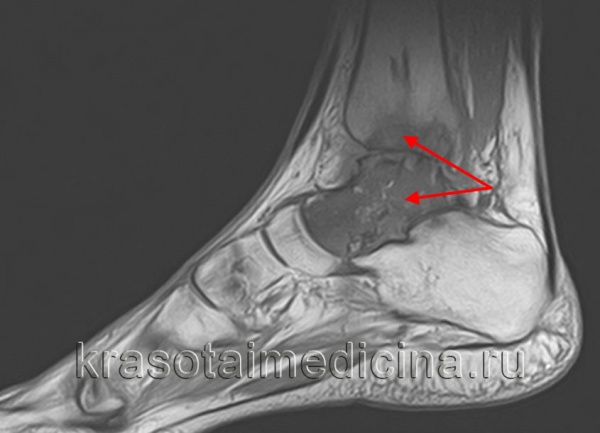

МРТ стопы. Остеомиелит таранной и большеберцовой кости с наличием обширной зоны деструкции костной ткани.

КТ стопы. Посттравматический хронический остеомиелит пяточной кости с наличием секвестра (красная стрелка) и свищевого хода (синяя стрелка).